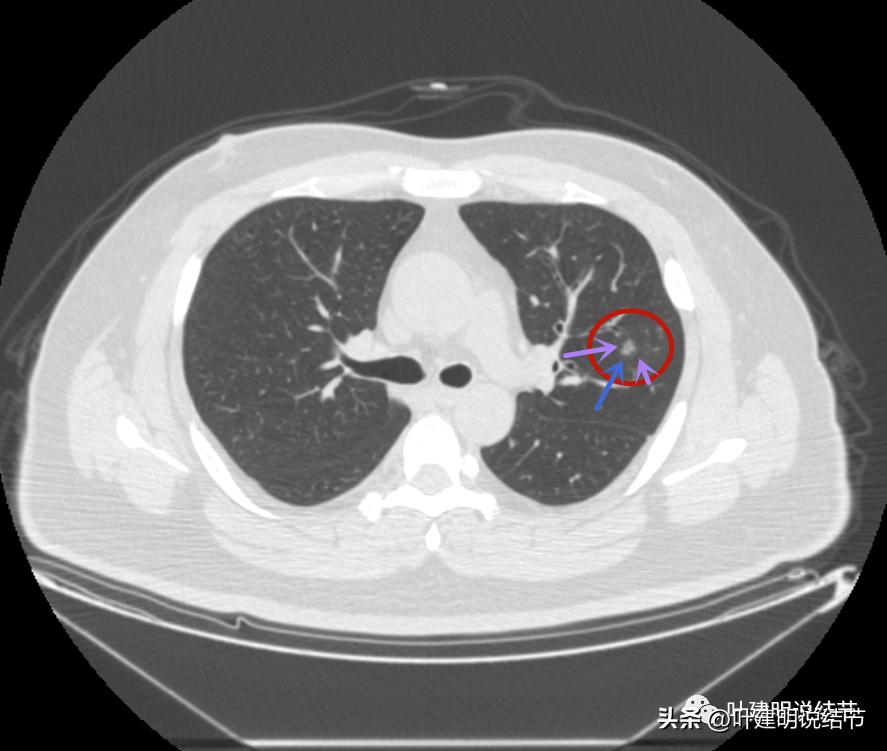

病灶3密度不均,轮廓清,有细毛刺样征(紫色箭头)

瘤现边界清

边上似乎有斑点状(绿色箭头),是不是卫星灶?

似乎有偏实性成分出现,密度较为杂乱

密度不均,瘤肺边界清,似乎是乱石征的影像

有偏实性成分,表面不平,边缘似乎有磨玻璃密度的成分

毛刺征(紫色箭头),微血管征(桔色箭头),实性点状成分(粉色箭头),整体轮廓较清(红色箭头)

血管弯征(桔色箭头)

血管进入

病灶3边缘部分的样子

感觉这两个病灶也是较为典型的恶性结节,但略不确定的是有的层面似乎有点像有卫星灶,再有就仍是这么多病灶集中在相对较小的区域内有点难以理解。